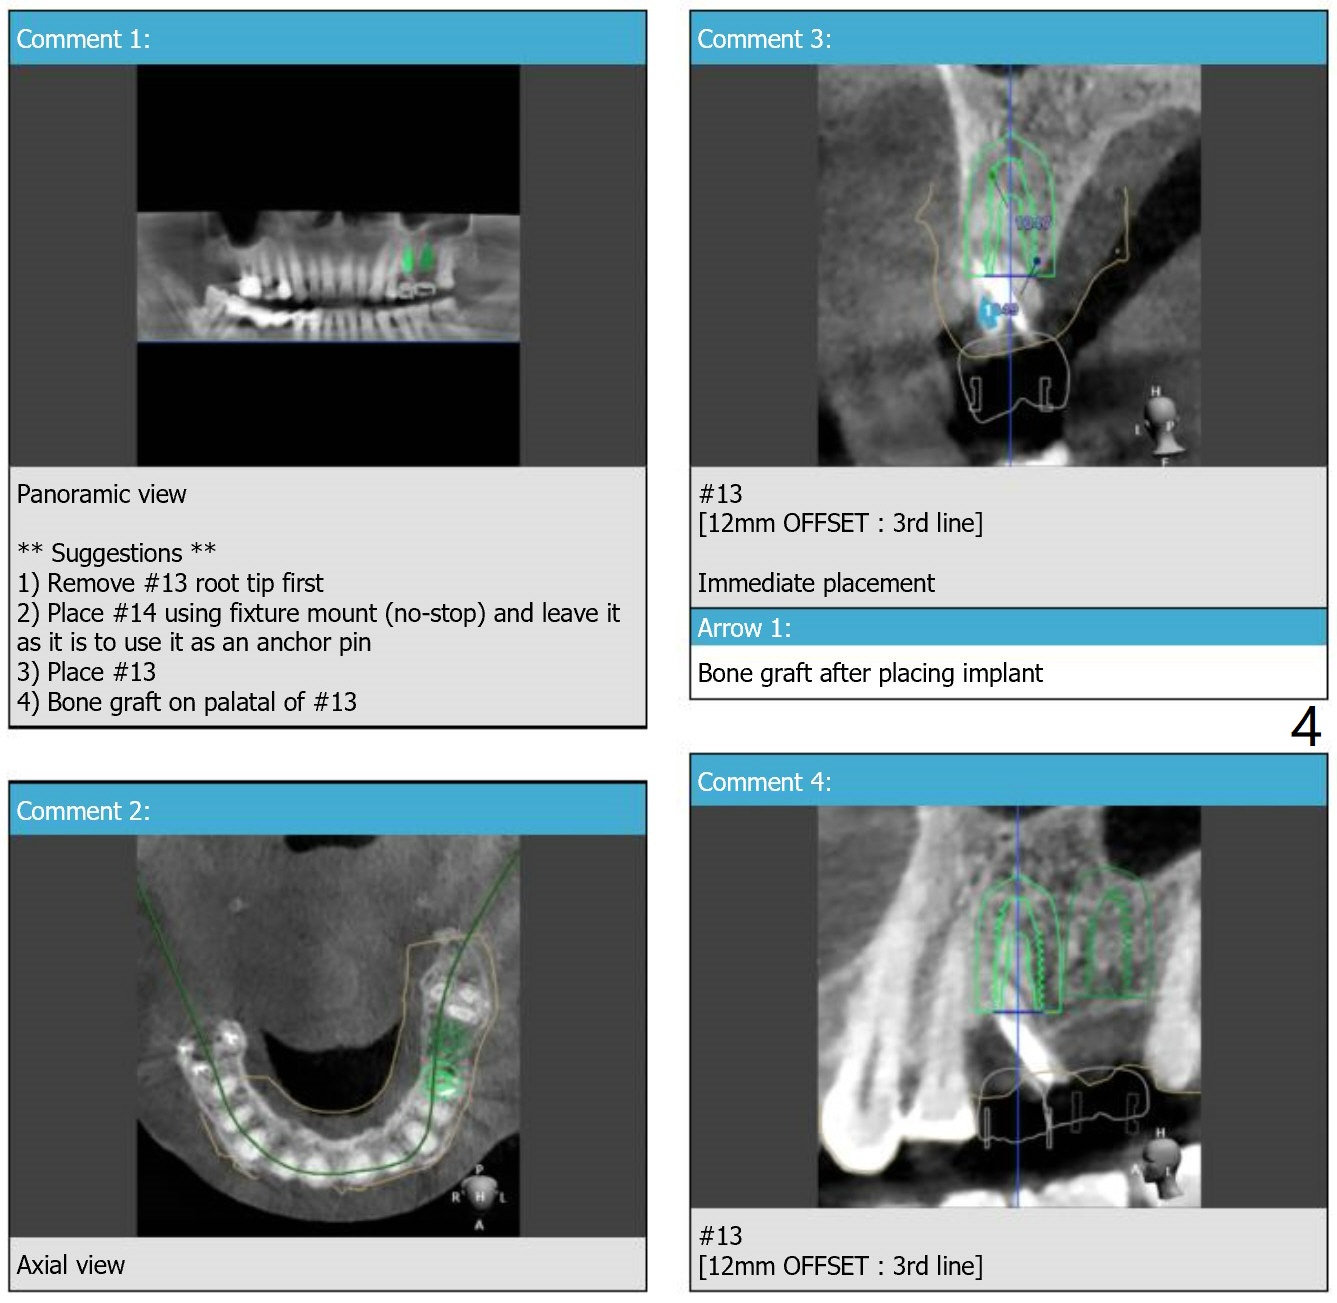

Return to Upper Molar Premolar Immediate Implant, Trajectory, Metronidazole